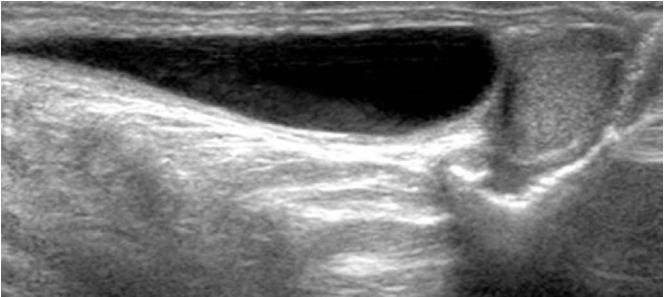

Groin lesions can be classified as neoplastic or non-neoplastic. Neoplastic lesions include lipoma, epidermoid cyst, angiomyofibroblastoma-like tumor, liposarcoma, and synovial sarcoma, as well as metastases from lymphoma, neuroendocrine carcinoma, and carcinomas of the lung, breast, urinary bladder, ovary, vulva, and colon. Non-neoplastic lesions include hernias, round ligament varices, endometriosis, Kimura disease, Castleman disease, hematoma, and inflammation. Because the clinical implications and therapeutic strategies for groin lesions vary depending on the cause, the ability to noninvasively differentiate among etiologies is very important. Although there is substantial overlap in ultrasonographic findings across various groin lesions, some ultrasonographic features, along with clinical characteristics, may suggest a specific diagnosis. Familiarity with the ultrasonographic and clinical features of various groin lesions facilitates accurate diagnosis and treatment.

腹股沟病变可分为肿瘤性或非肿瘤性。肿瘤性病变包括脂肪瘤、表皮样囊肿、血管肌纤维母细胞瘤样肿瘤、脂肪肉瘤和滑膜肉瘤,以及淋巴瘤、神经内分泌癌和肺癌、乳腺癌、膀胱癌、卵巢癌、外阴癌及结肠癌的转移瘤。非肿瘤性病变包括疝、圆韧带静脉曲张、子宫内膜异位症、木村病、卡斯特曼病、血肿和炎症。由于腹股沟病变的临床意义和治疗策略因病因不同而异,因此无创鉴别病因的能力非常重要。尽管各种腹股沟病变的超声表现有很大重叠,但一些超声特征结合临床特点可能提示特定诊断。熟悉各种腹股沟病变的超声和临床特征有助于准确诊断和治疗。